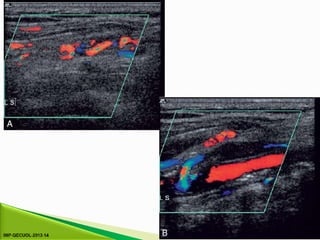

⦁ 1. Colour Doppler may show the presence of collateral vessels

in the muscles of the thigh (Fig. 4-3A).

⦁ 2. Collateral vessels may be seen leaving the main artery (Fig.

4-3B).

⦁ Indirect signsof significant disease ⦁ There are three indirect signs of significant disease ⦁ 1. Colour Doppler may show the presence of collateral vessels in the muscles of the thigh (Fig. 4-3A). ⦁ 2. Collateral vessels may be seen leaving the main artery (Fig. 4-3B). ⦁ 3. The character of the spectral waveform may show a change between two levels, indicating a segment of disease somewhere between the two points of measurement.